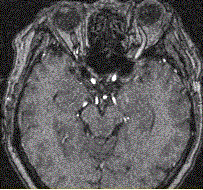

问题 女性,62岁。外伤后左侧突眼。MRI显示如下图。 该病可能的诊断是

选项 A.海绵状血管瘤 B.发育性静脉畸形 C.AVM D.毛细血管扩张症 E.动脉瘤 F.左侧颈内动脉海绵窦瘘 G.moyamoya

答案 F